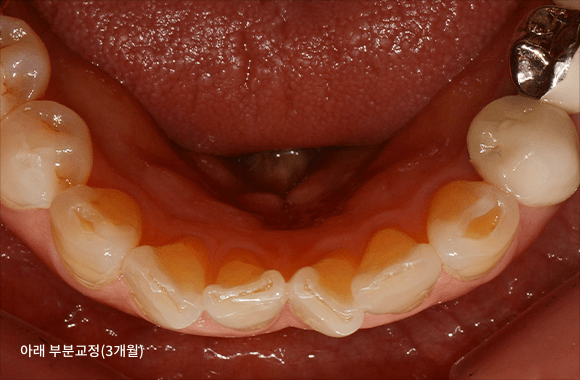

시니어 부분교정